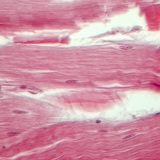

400x magnification

Biology